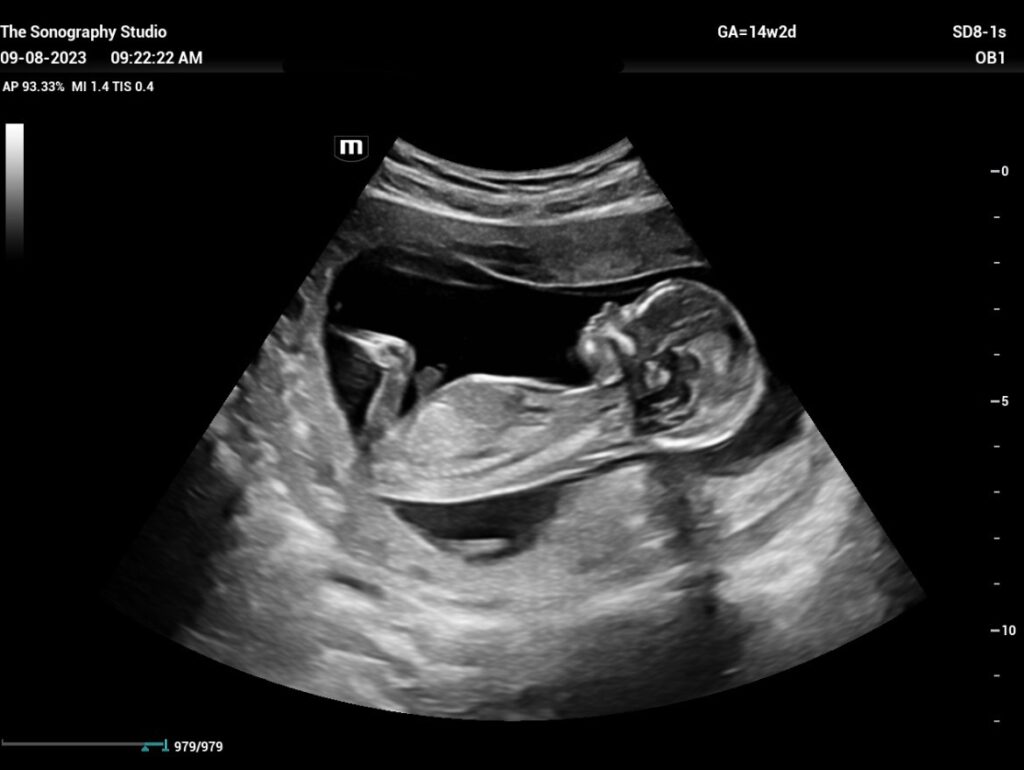

Ultrassonografia Obstétrica

Acompanha a gestação e o desenvolvimento do bebê, conforme a fase e a necessidade clínica.

Ultrassonografia Morfológica

Exame mais detalhado da gestação para avaliar a anatomia do bebê.